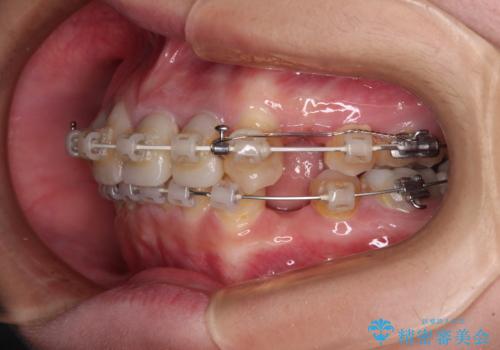

- 矯正装置

- 審美装置

- 前歯のデコボコと、その結果むし歯が進行していることを気にして来院された患者様です。

前歯や奥歯の根管治療を行い、その後上下左右の第一小臼歯4本を抜歯してワイヤー装置にて矯正治療を行うこととしました。